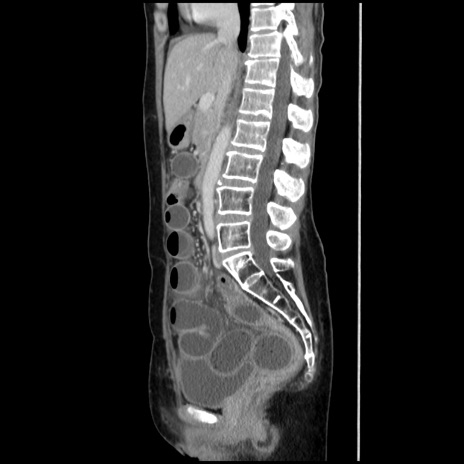

症例32(矢状断像)

【症例】40歳代 女性

【主訴】上腹部痛、嘔気・嘔吐

【現病歴】約9時間前頃から急に上腹部痛、嘔気、嘔吐が出現。改善しないため救急要請。

【既往歴】子宮頚癌(広汎子宮全摘術、放射線療法)、腸閉塞

【身体所見】腹部:平坦、軟、腸雑音亢進、上腹部を中心に腹部全体に圧痛あり。

【データ】WBC 8400、CRP 0.03